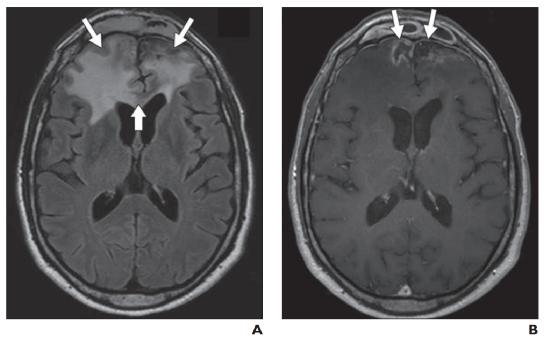

图7——肿瘤血管源性水肿。A,在伴有颅内黑色素瘤转移的1型水肿患者中,增强T1-加权图像显示右侧额叶和左侧顶叶的增强肿块(箭头)。B,FLAIR序列显示与A相同的病灶周围水肿,界限清楚,局限于肿块附近(箭头)。C,在多灶性多形性胶质母细胞瘤2型水肿患者中,对比增强T1加权成像显示左侧枕叶有多个强化病灶(箭头)。D,FLAIR序列显示弥漫性浸润性水肿(箭头),反映肿瘤微浸润。穿过胼胝体压部中线(星号)。

上图已经描述了两种不同类型的瘤周血管源性水肿。1 型可见于低级别和非神经胶质肿瘤的紧邻区域,例如脑膜瘤和转移瘤。这种类型被认为继发于脑实质压迫,继发性缺血和坏死甚至在肿瘤切除后仍然存在(图 7A )。2 型水肿发生在高度浸润性高级别神经胶质瘤中,会引起血脑屏障的额外紊乱。这种水肿模式遍及同侧大脑半球,指状突起反映肿瘤微浸润(图 7B )。切除后,数月内水肿可能会部分或完全消退。与 1 型水肿相比,2 型水肿 DWI 的扩散系数增加,DTI 的各向异性分数降低,这可能反映了恶性细胞浸润造成的实质破坏更大。当见于小肿瘤或良性肿瘤时,这种非典型水肿模式高度怀疑恶性变性。